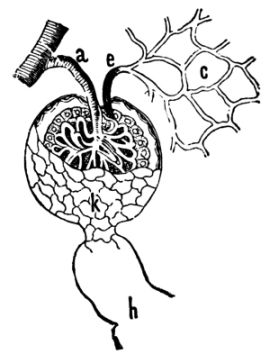

The Abdominal Cavity, 132—Muscles of the Abdomen, 132—The Peritoneum, 134—Abdominal Regions, 134—Salivary Digestion, 136—The Pharynx, 139—The Esophagus, 138—The Stomach, 138—Gastric Digestion, 139—Vomiting, 140—Intestinal Canal, 141—The Small Intestine, 142—Intestinal Digestion, 143—Absorption in Intestine, 144—The Large Intestine, 145—Food and Metabolism, 147—The Liver, 149—The Gall-bladder, 152—The Pancreas, 153—The Spleen, 153—The Suprarenal Capsules, 154—The Kidneys, 155—The Urine, 156—The Ureters, 159—The Bladder and Urethra, 159. |